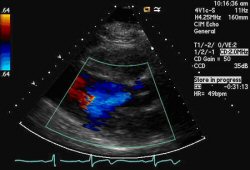

Aortic regurgitation AR occurs when there is backflow of blood from the aorta into the left ventricle during ventricular diastole. Aortic regurgitation is associated with an early diastolic murmur heard loudest at the left sternal edge Aetiology. Aortic Valve Regurgitation Mitral Valve Regurgitation.

Example Of A Jet Of Aortic Regurgitation As Shown By Color Flow Imaging Download Scientific Diagram